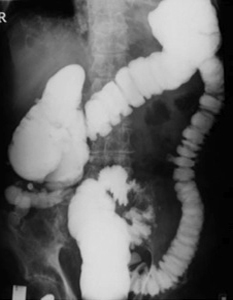

Lavement baryte :

C'est examen radiologique du gros intestin

avec le produit de contrast introduit par voie rectale et

les cliche expose sont en prise durant de l'examen . De 1

litre - 1,5 litre de baryum est injecte par voie rectale au

colon descendent , colon trasverse , colon montant et une

parties de ileon .Tout cardre du colon soit opacifie . Et

apres evacuation du cardre colique le plus complete possible

, l,insufflation de air et une rotation complete du sujet

sur lui meme pour repartition complete de la supention

barytee sur la paroi colique . Image radiologique obtenir

soit en double de contrast .

| Images radiologique du colon (

lavement baryte mono contrast ) La sigmoide , colon

descendent , colon transverse sont en bien vue .

Angle du foie du colon et colon ascendent sont

superpose . Un parties de ileum se voyait bien sur

le cliche |